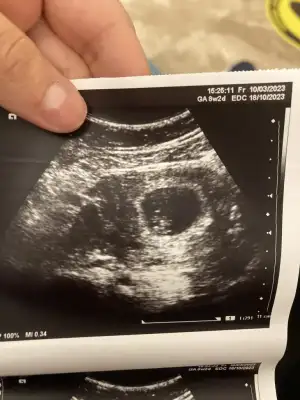

MAŞALLAH CANIM NASIL ÇIKTI HAFATSIYLA UYUMLUMU ? DOKTOR NE DEDİ :)

Bizim seninle aynı canım 8+6 tüp bebek benimde aynı gerginlik bendede sağlıkcakla gelsinler inşallahAmin canım amin hepimizin sonuçları güzel olur inşallah.

Bugün benim kontrolüm var çok korkuyırum kötü bir haber alırım diye belim ağrıyor onun dışında hiç birşeyim yok iyiym ilk başarılı tüp bebeğim olacak inşallah herşey yolundadır hep araftayım Allahım sağlıklı haber almak nasip olur inşallah. 8+6 bugün çok korkuyorum kalbi durmuş haberini alırız diye. Rabbim bizlere herşeyin hayırlısını nasip etsin sağlıkla evlatlarımızı kucağımıza almak nasip olsun.